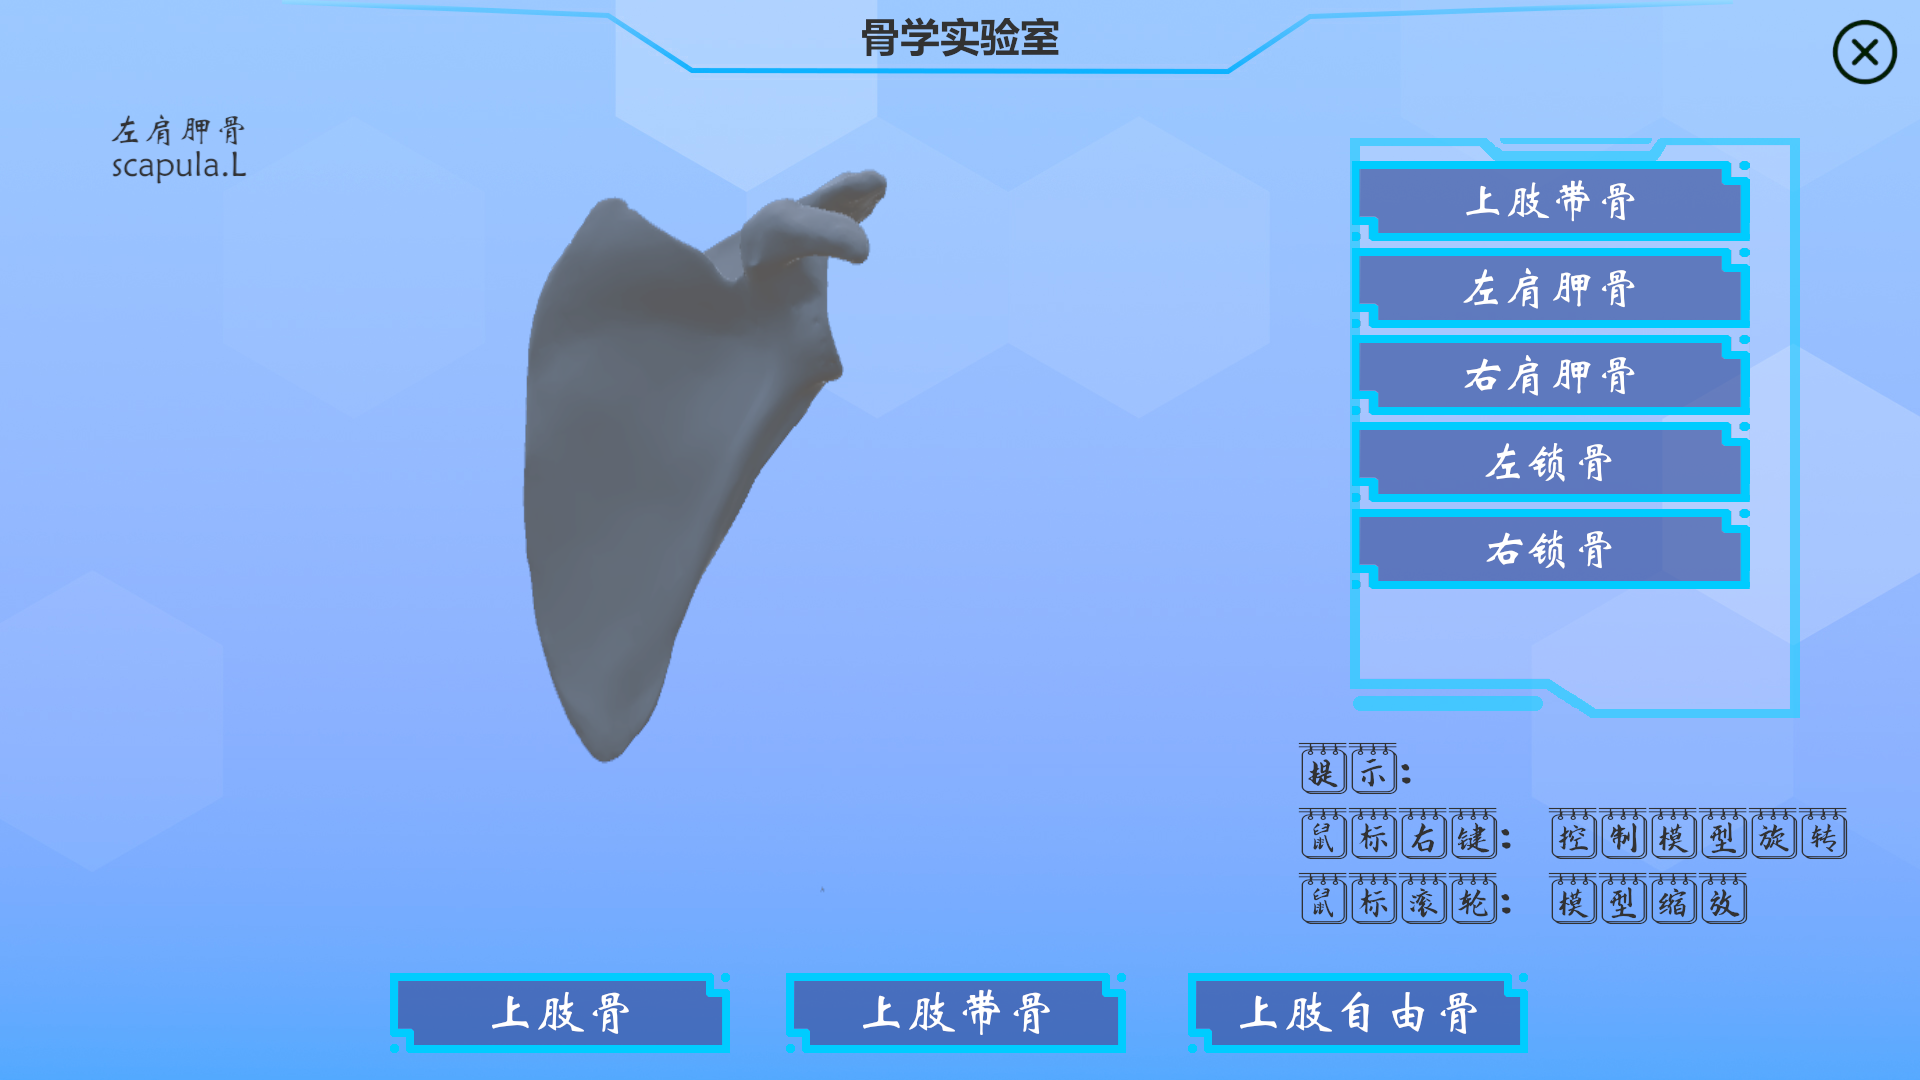

功能集成,目前包括人体解剖学教学、组织学胚胎学教学、介入手术教学、影像学教学等功能

本产品打破以往产品功能单一的局面,目前具有解剖教学、组胚教学、影像教学、模拟介入手术等功能

解剖教学模块内置了人体全骨骼标本,你可以根据系统索引进行学习

以下是产品内截图实况